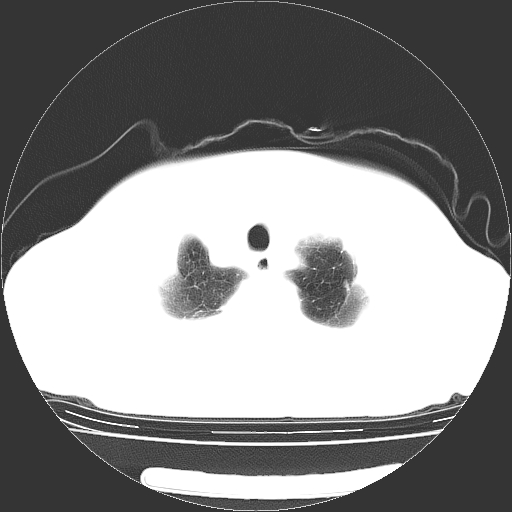

女,70岁,咳嗽、咳痰一个月,低热一周。

1.左上肺结核,部分纤维化。右肺中下叶部分肺不张,内见液化、坏死及点状钙化,右中下叶支气管壁增厚、管腔狭窄,见多个点状钙化,结合临床考虑支气管内膜结核,建议痰检查抗酸杆菌并参考血沉。两肺多个小圆点状高密度灶,境界模糊,多考虑结核肺内播散。但本人年龄较大首先应支气管镜检以除外右肺癌。

一元论:内膜结核伴下肺阻塞性肺炎并双肺播散!另:主动脉夹层。右侧少量胸腔积液。

支持,首先一元论解释。胸主动脉部分层面环形低密度,中心强化。环形影不强化。不象真假腔的改变。我考虑动脉炎,不太支持夹层动脉瘤-和大家的观点不一致,希望楼主让患者再做个心血管的彩超吧。